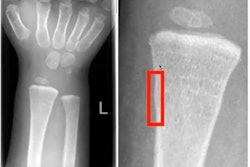

Between April 2019 to April 2020, 1.2 million patients presented to an emergency department in the U.K. with acute fractures or dislocations, an increase of 23% from the year before. Missed or delayed diagnosis of fractures on radiographs is a common diagnostic error, ranging from 3% to 10%. Thus, an increasing number of studies apply artificial intelligence (AI) techniques to fracture detection as an adjunct to clinician diagnosis, the authors wrote.

Thirty-seven studies identified fractures on radiographs, of which 18 focused on lower limb, 15 on upper limb, and four on other fractures. Five studies identified fractures on CT images.